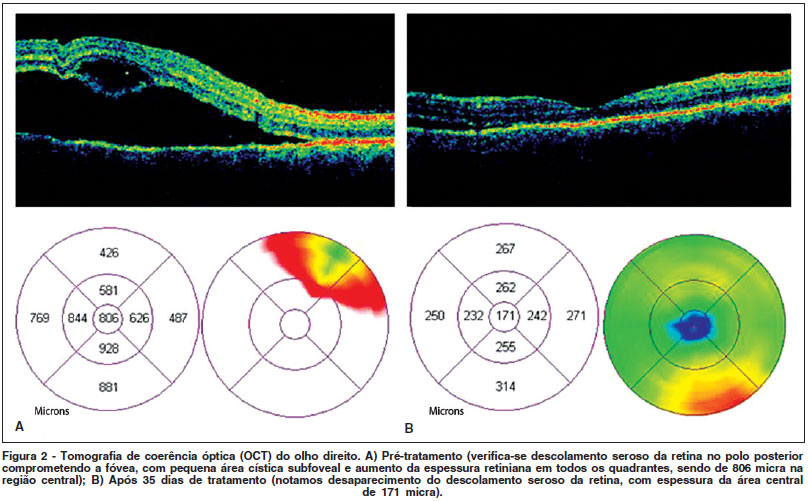

A angiofluoresceinografia mostrou múltiplos pontos de vazamentos perimaculares com aspecto característico de "pin point" e a tomografia de coerência óptica (OCT) registrou extensa área de descolamento seroso retiniano (Figura 2A). O paciente recebeu 140 mg/dia de corticosteróide (Meticorten®), com redução gradual (10 mg/semana), evoluindo com melhora importante da acuidade visual e do descolamento retiniano já na primeira semana de tratamento. Com 35 dias de corticoterapia, apresentava acuidade visual de 20/25 parcial e resolução completa do descolamento de retina (Figura 2B). A retinografia após 60 dias de tratamento está representada na figura 1B, evidenciando melhora substancial.

A tomografia de coerência óptica (OCT), apesar de descrita há mais de dez anos, tem emergido como uma nova técnica que, através de imagens de alta resolução de cortes seccionais da retina, pode auxiliar no diagnóstico, na monitorização e na análise quantitativa de doenças que acometem a mácula e a cabeça do nervo óptico(8-10). No caso descrito anteriormente, realizamos a OCT precocemente, evidenciando edema e descolamento seroso da retina. Após 35 dias de tratamento, pudemos acompanhar a resolução do quadro através de nova OCT, corroborando dados sugestivos de prognóstico favorável dos casos de oftalmia simpática submetidos a tratamento médico precoce(10).